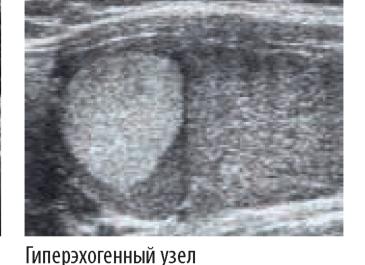

- гиперэхогенным (с повышенной отражающей способностью)

Гиперэхогенностью обладают очаги с высокой плотностью и, соответственно, низким содержанием воды. Это чаще всего связано с преобладанием в них соединительнотканного компонента или отложениями кальция. Гиперэхогенными являются некоторые доброкачественные и злокачественные опухоли (аденома, папиллярный рак), включения обызвествлений (кальцинаты).